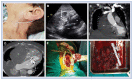

Extrapericardial cardiac tamponade due to massive retrosternal hematoma